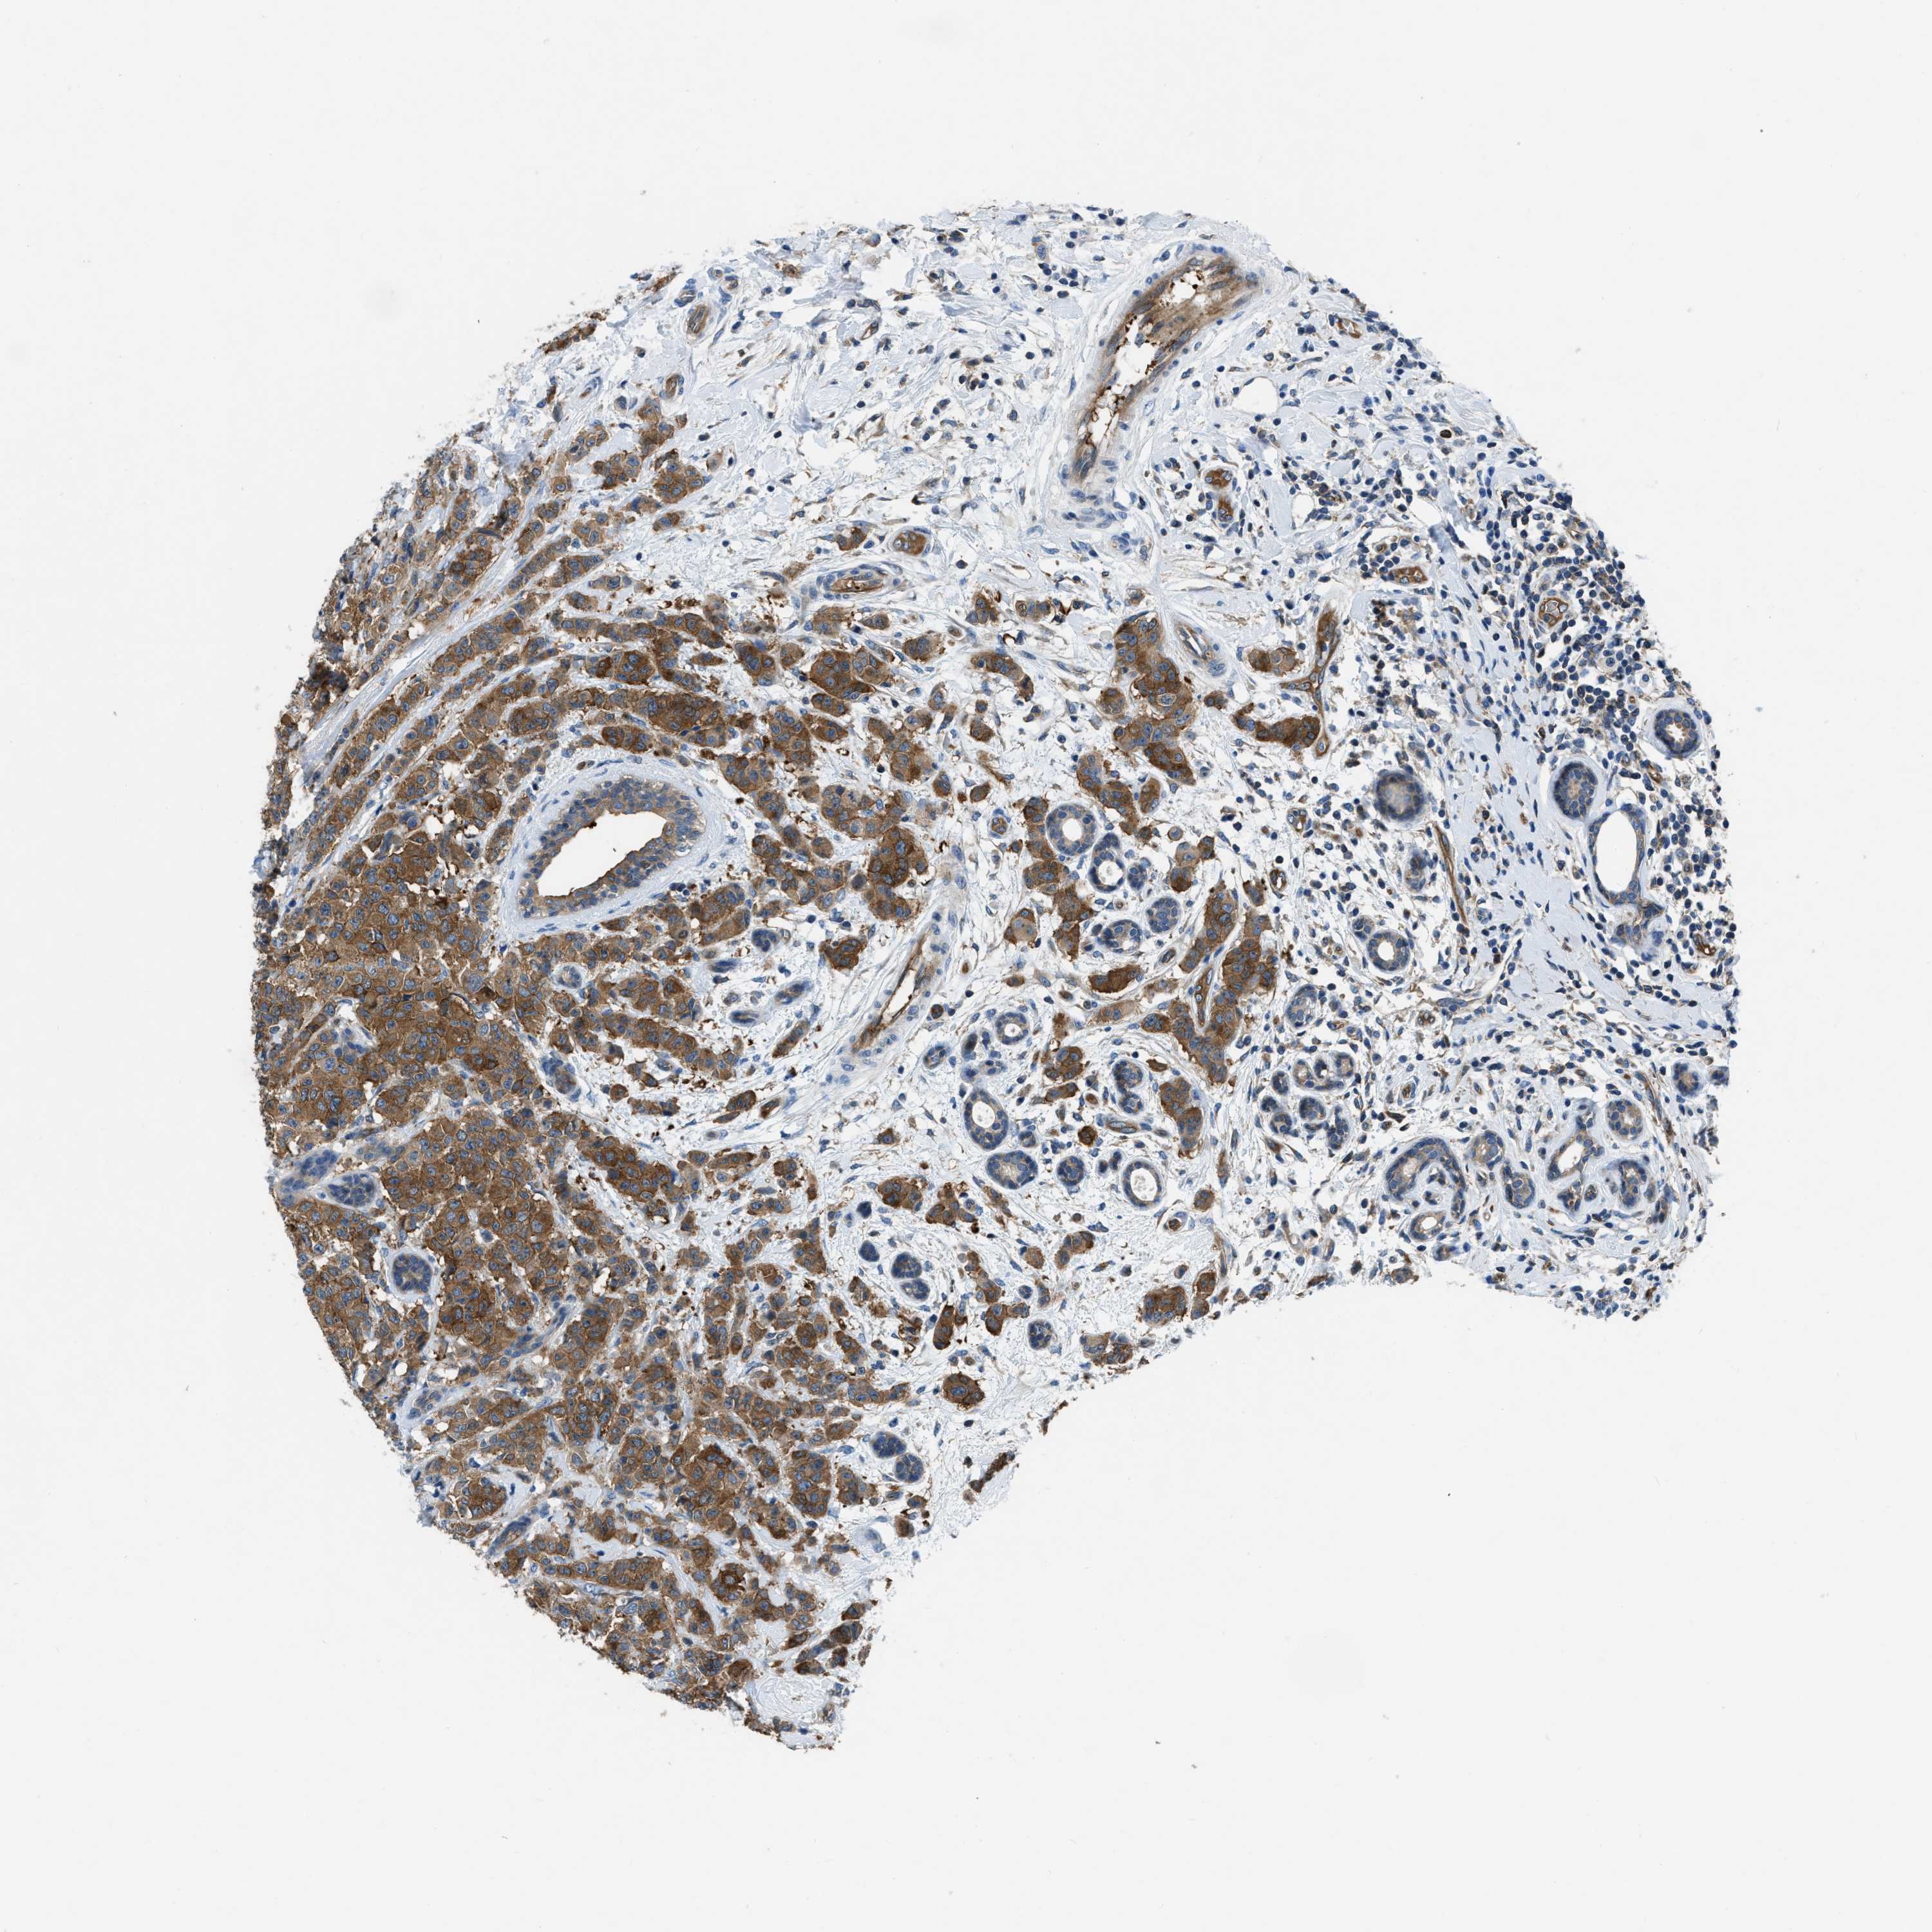

CANCER BREAST CANCER Show tissue menu

BRCA TCGA BRCA VALIDATION PROTEIN EXPRESSION